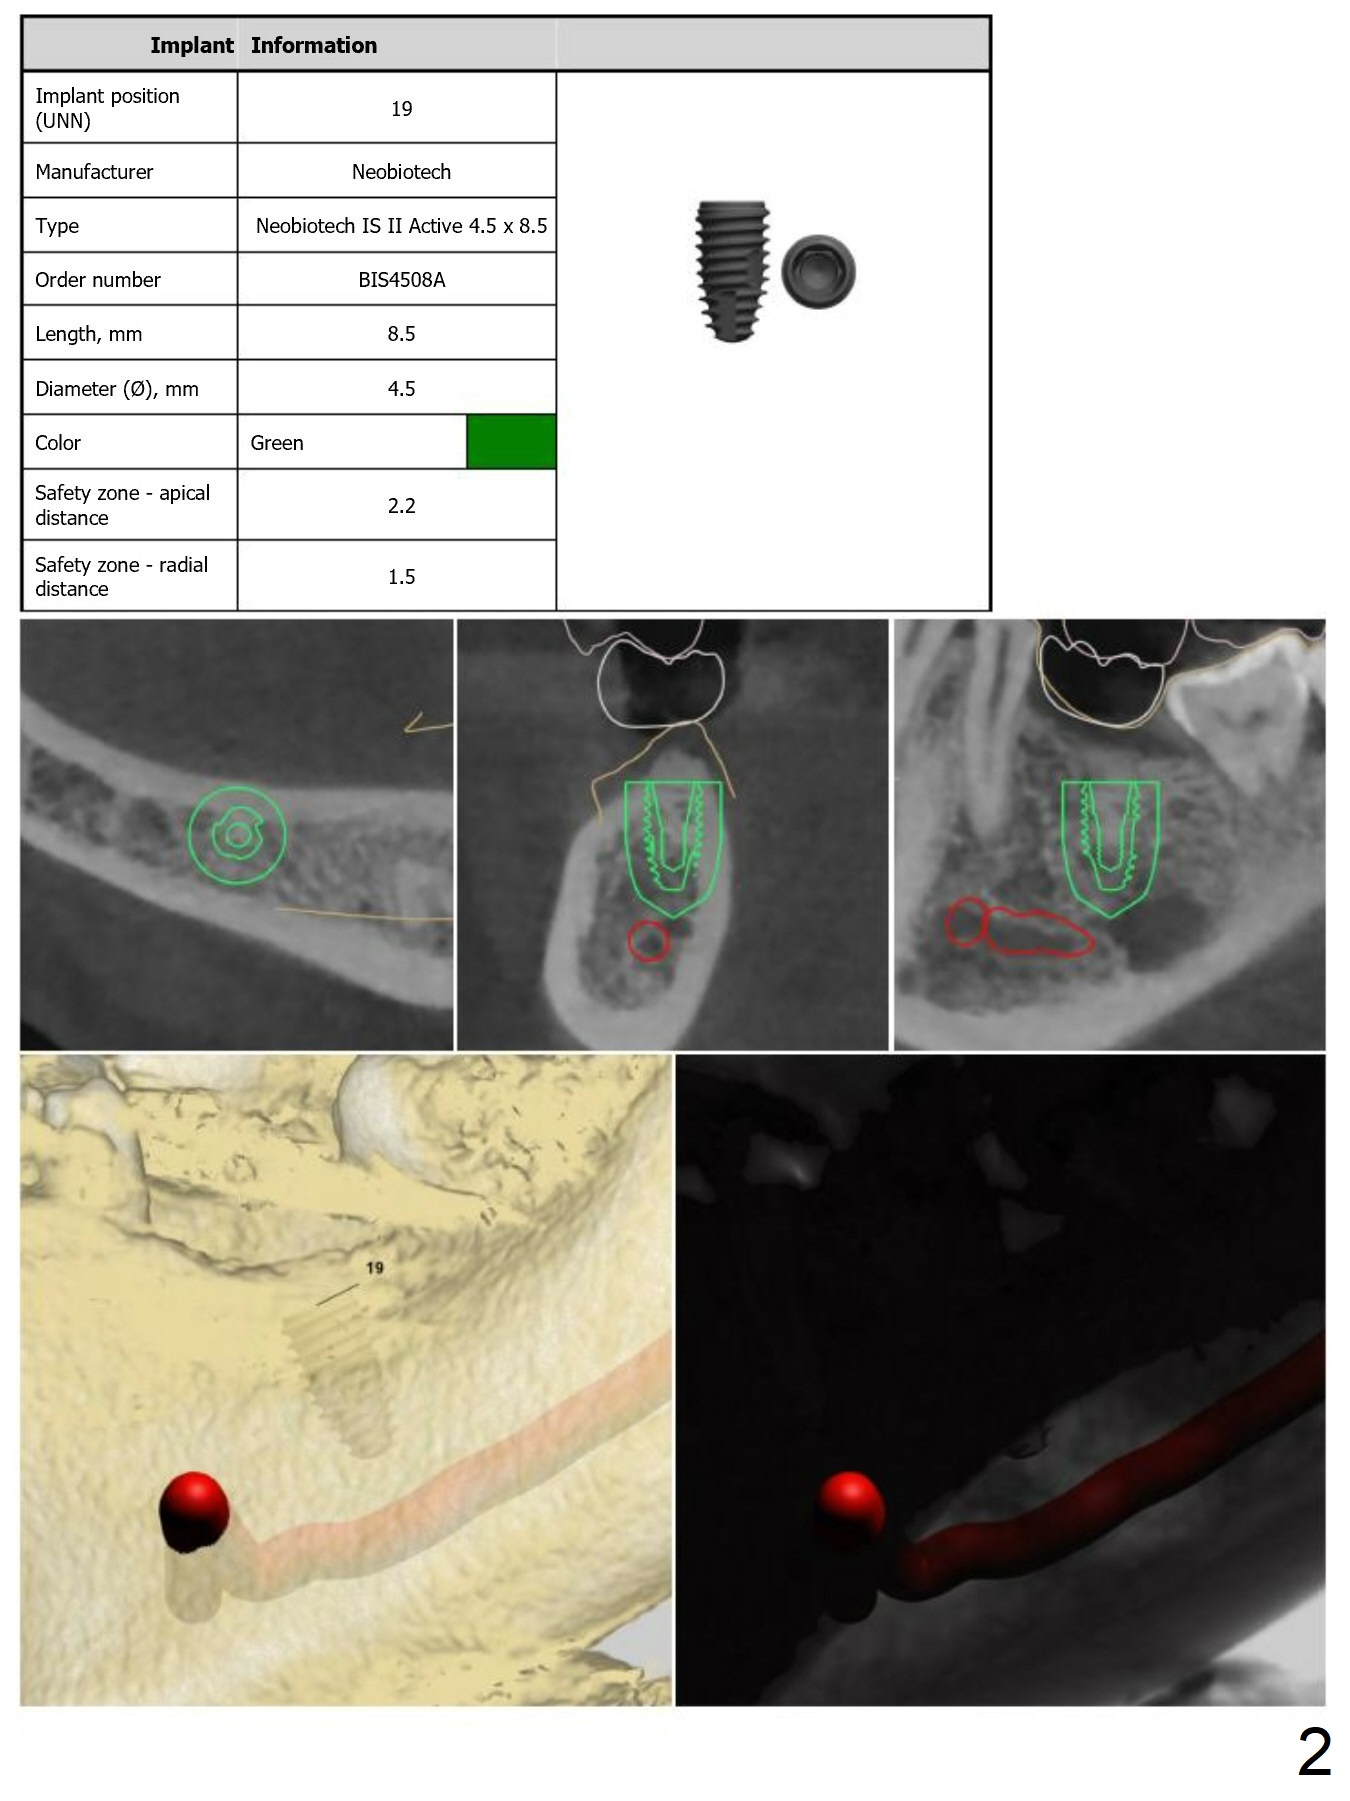

Guided surgery will be conducted at #19 post mini-implant placement for the opposing tooth intrusion.